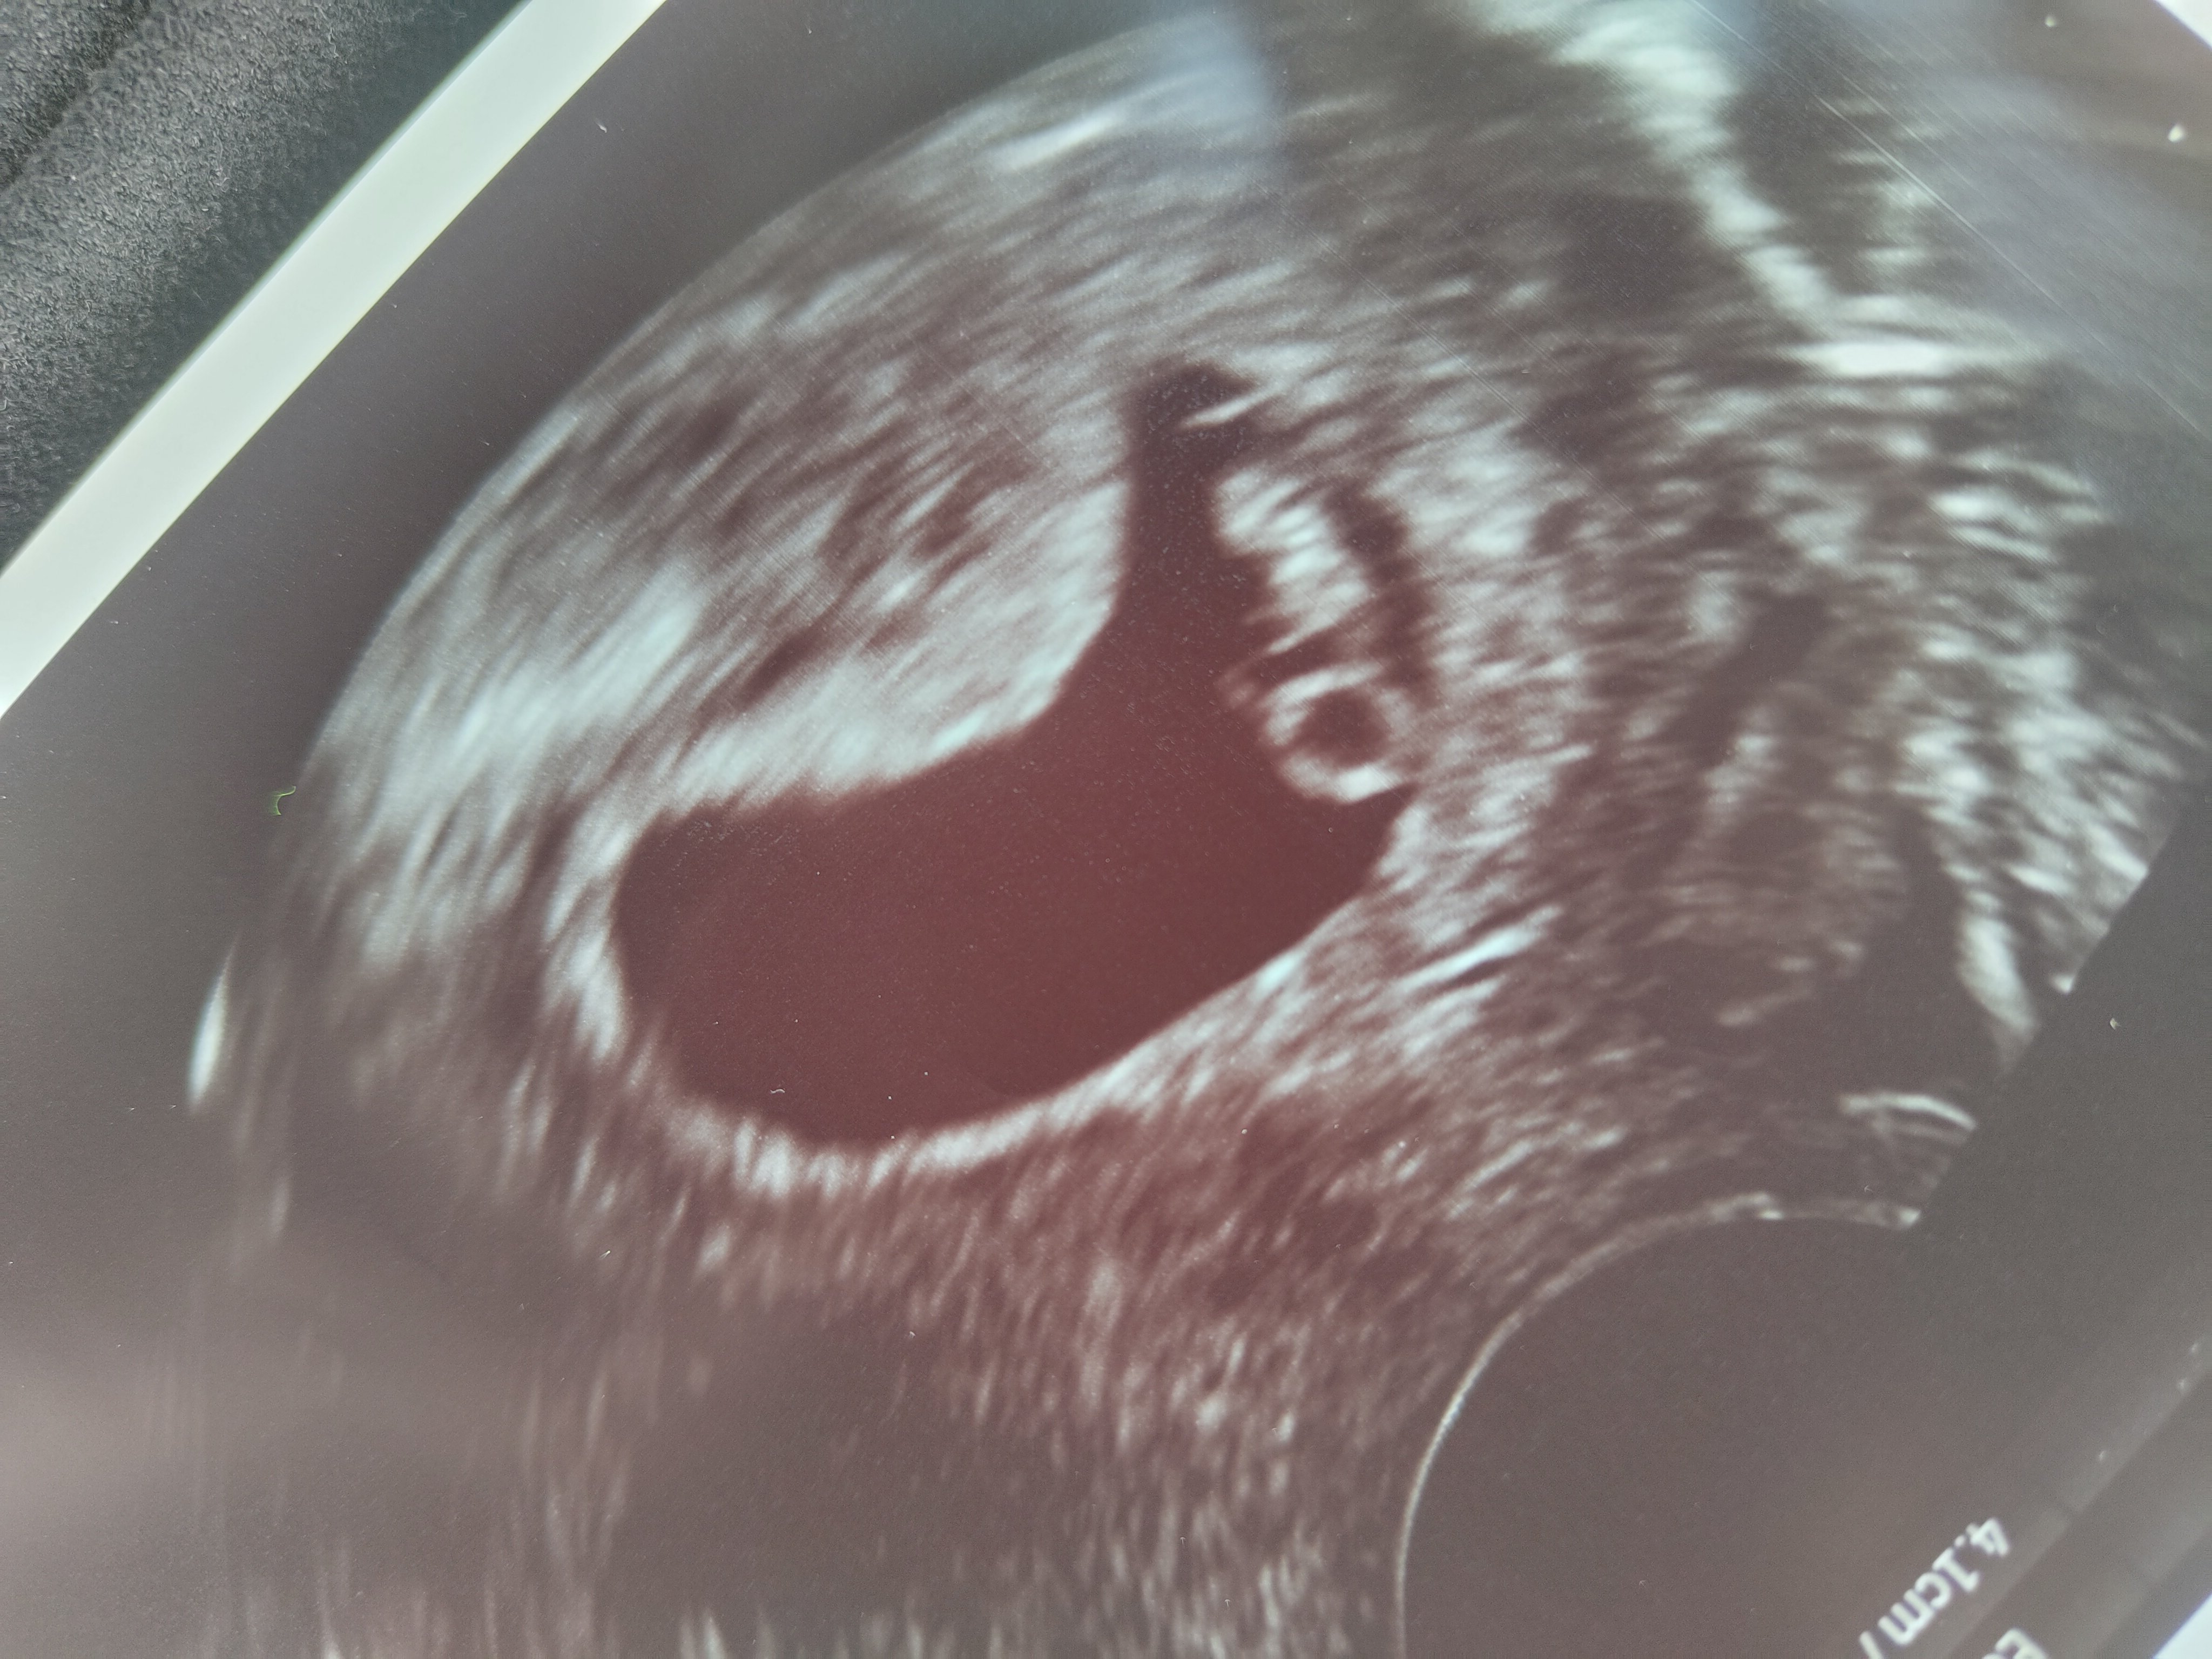

Første svangerskapskontroll 8+3 (eller 8+4)

I morgen er det ultralyd på sykehuset!

Nervøs, men håper på det beste. Om alt er bra, så regner jeg med at jeg ikke får flere ekstra ultralyder offentlig. Så da blir jo evt neste otul. Jordmor sa de likte å ta den etter fullgåtte uke 13.